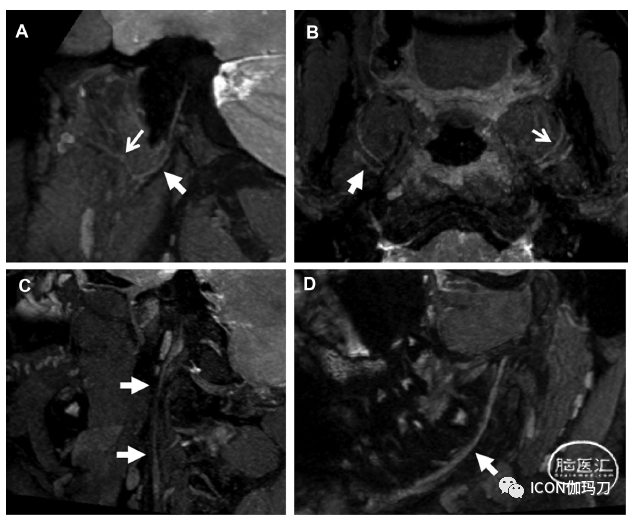

几乎所有与颅神经纤维束示踪造影有关的研究都涉及后窝肿瘤中的面神经-前庭耳蜗神经复合体(address the facial-vestibulocochlear nerve complex in the context of posterior fossa tumors)(图1),因为在切除肿瘤过程中的疏忽,造成面神经损伤,会使人衰弱(只有70% - 80%的大于3cm的前庭神经鞘瘤[VSs],能保留面神经功能)。尽管由于肿块占位效应和解剖变形,常规的MR解剖序列通常无法演绎显示(a priori visualization)面神经-前庭耳蜗神经复合体的面神经成分,但纤维束示踪成像已被证明是一种有前景的替代方法。对纤维束示踪成像在前庭神经鞘瘤(VS)术前神经定位中应用的系统综述,发现纤维束示踪成像和手术结果的总体一致性率(overall rate of concordance)为87.1%,不一致性率(discordance)为7.6%,生成纤维束示踪成像失败率(failure of tract generation)为3.4%。然而,最近的综述发现颅神经纤维束示踪成像的准确性范围差异很大(30% - 100%)。

图1。前庭神经鞘瘤的DTT检查例。DTT数据与3D建设性干扰(CISS)序列共同记录了一个以听道孔为中心的左侧小前庭神经鞘瘤患者。使用MRtrix 3.0和概率算法(CSD)生成的纤维束示踪成像流线。(A)配准轴位图像显示左侧神经鞘瘤周围沿面神经线向前(灰色箭头)和前庭耳蜗神经线向后(黑色箭头)延伸的流线。(B)通过左侧内听道的配准斜位矢状序列显示流线束的移位,它们聚集在左侧前庭神经鞘瘤的正上方(灰色箭头)和后外侧(黑色箭头)(分别在面神经和前庭耳蜗神经的近似轨迹中)。